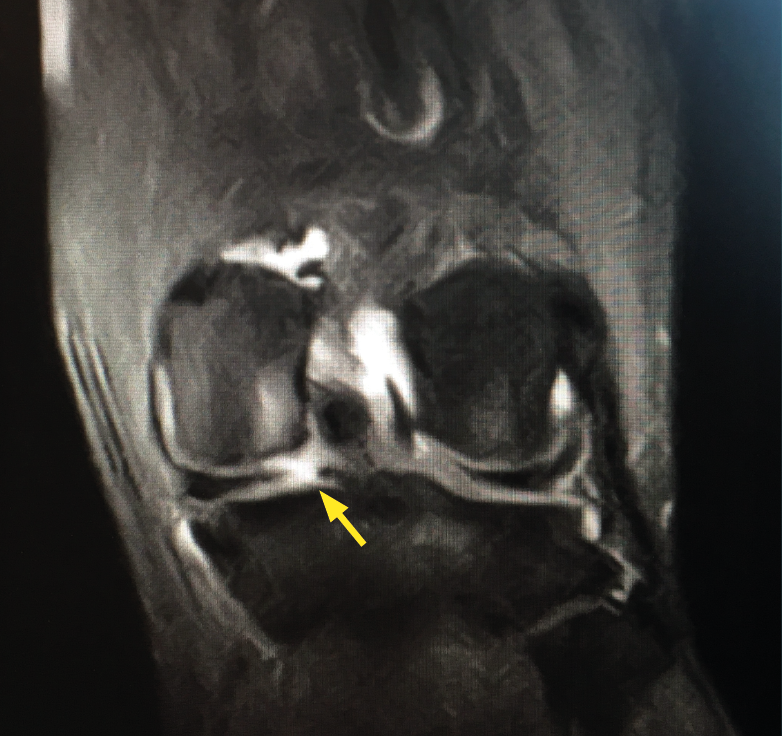

Una lesión de la raíz, aunque permanezca intacto el resto de la circunferencia del menisco, va a producir una extrusión del mismo y biomecánicamente es equivalente a una meniscectomía total en cuanto a las presiones de contacto en la rodilla se refiere(38). Este efecto puede hacer progresar la rodilla hacia un rápido deterioro, como demostró un estudio del grupo de la Mayo en Rochester, en el que un 31% de los pacientes alrededor de los 60 años con lesión de raíz meniscal posterior no reparada en menos de 3 años necesitaron un reemplazo total de rodilla(39)(Figura 10).

Figura 10. Imagen de resonancia magnética, corte coronal, donde se aprecia una lesión de raíz meniscal posterior del menisco medial en una rodilla izquierda. La flecha amarilla muestra la zona exacta de la lesión. Puede observarse también un intenso edema óseo a nivel del cóndilo femoral medial secundario al estrés de carga provocado por la lesión meniscal.

Respecto a los resultados que podemos esperar de la reparación de la raíz meniscal, depende de muchos factores, pero en general la mayoría de los trabajos y revisiones han demostrado buenos resultados y, sobre todo, mejores que ignorando la lesión o realizando una meniscectomía. Un reciente trabajo con second-look observó una tasa de curación o cicatrización completa del 69,7%; asmismo, se vio que cuando había cicatrización completa el resultado clínico era mejor y hubo un menor número de cambios degenerativos en estos pacientes(40).